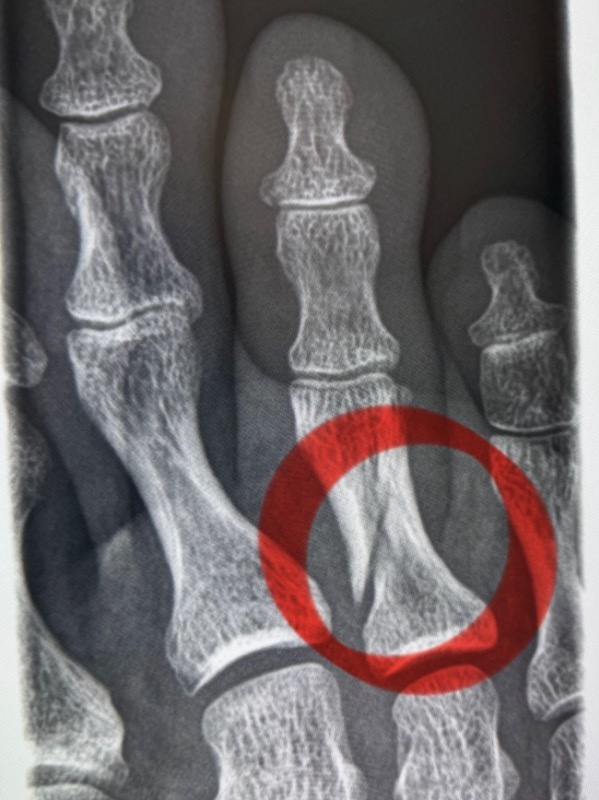

わたしの右の第3趾(中趾、中指)、折れていました。

9月15日(月、祝)、我が子の野球チームが体育館で練習をしていた時のことです。わたしは右足親指以外の4本を、置いてあった平均台で痛打しました。それなりの音がしましたし、痛みはもちろん、かなり腫れていたので「折れているかもなあ」とは思っていました。

で、「折れていますね」と(笑い)。45年ぶりくらいの骨折のはずです。

ただ、歩いているし、いまさらギプスしましょうでもなく、「このままいきましょう」となりました。折れた指の両隣をテープでくっつけて、あとは湿布で対処していきます。